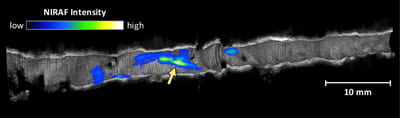

Combining optical coherence tomography (OCT) with near-infrared autofluorescence (NIRAF) imaging may more accurately identify coronary artery plaques that are most likely to rupture and cause a heart attack. OCT provides images of tissue microstructure but not of its chemical and molecular composition. Since both of those characteristics are needed to fully understand coronary artery disease, the combination of OCT with NIRAF could provide a more powerful tool for investigating coronary pathology.

The detailed images provided by OCT are created by bouncing near-infrared light off the internal surfaces of blood vessels, and can identify plaques that have the appearance of rupture-prone “vulnerable” plaques with the potential to cause a heart attack or sudden cardiac death. Fluorescence imaging techniques like NIRAF illuminate an artery with a specific wavelength of light to excite certain molecules, which respond by emitting different wavelengths. Since only certain molecules respond, the resulting signal provides information on the molecular composition of analyzed tissue.